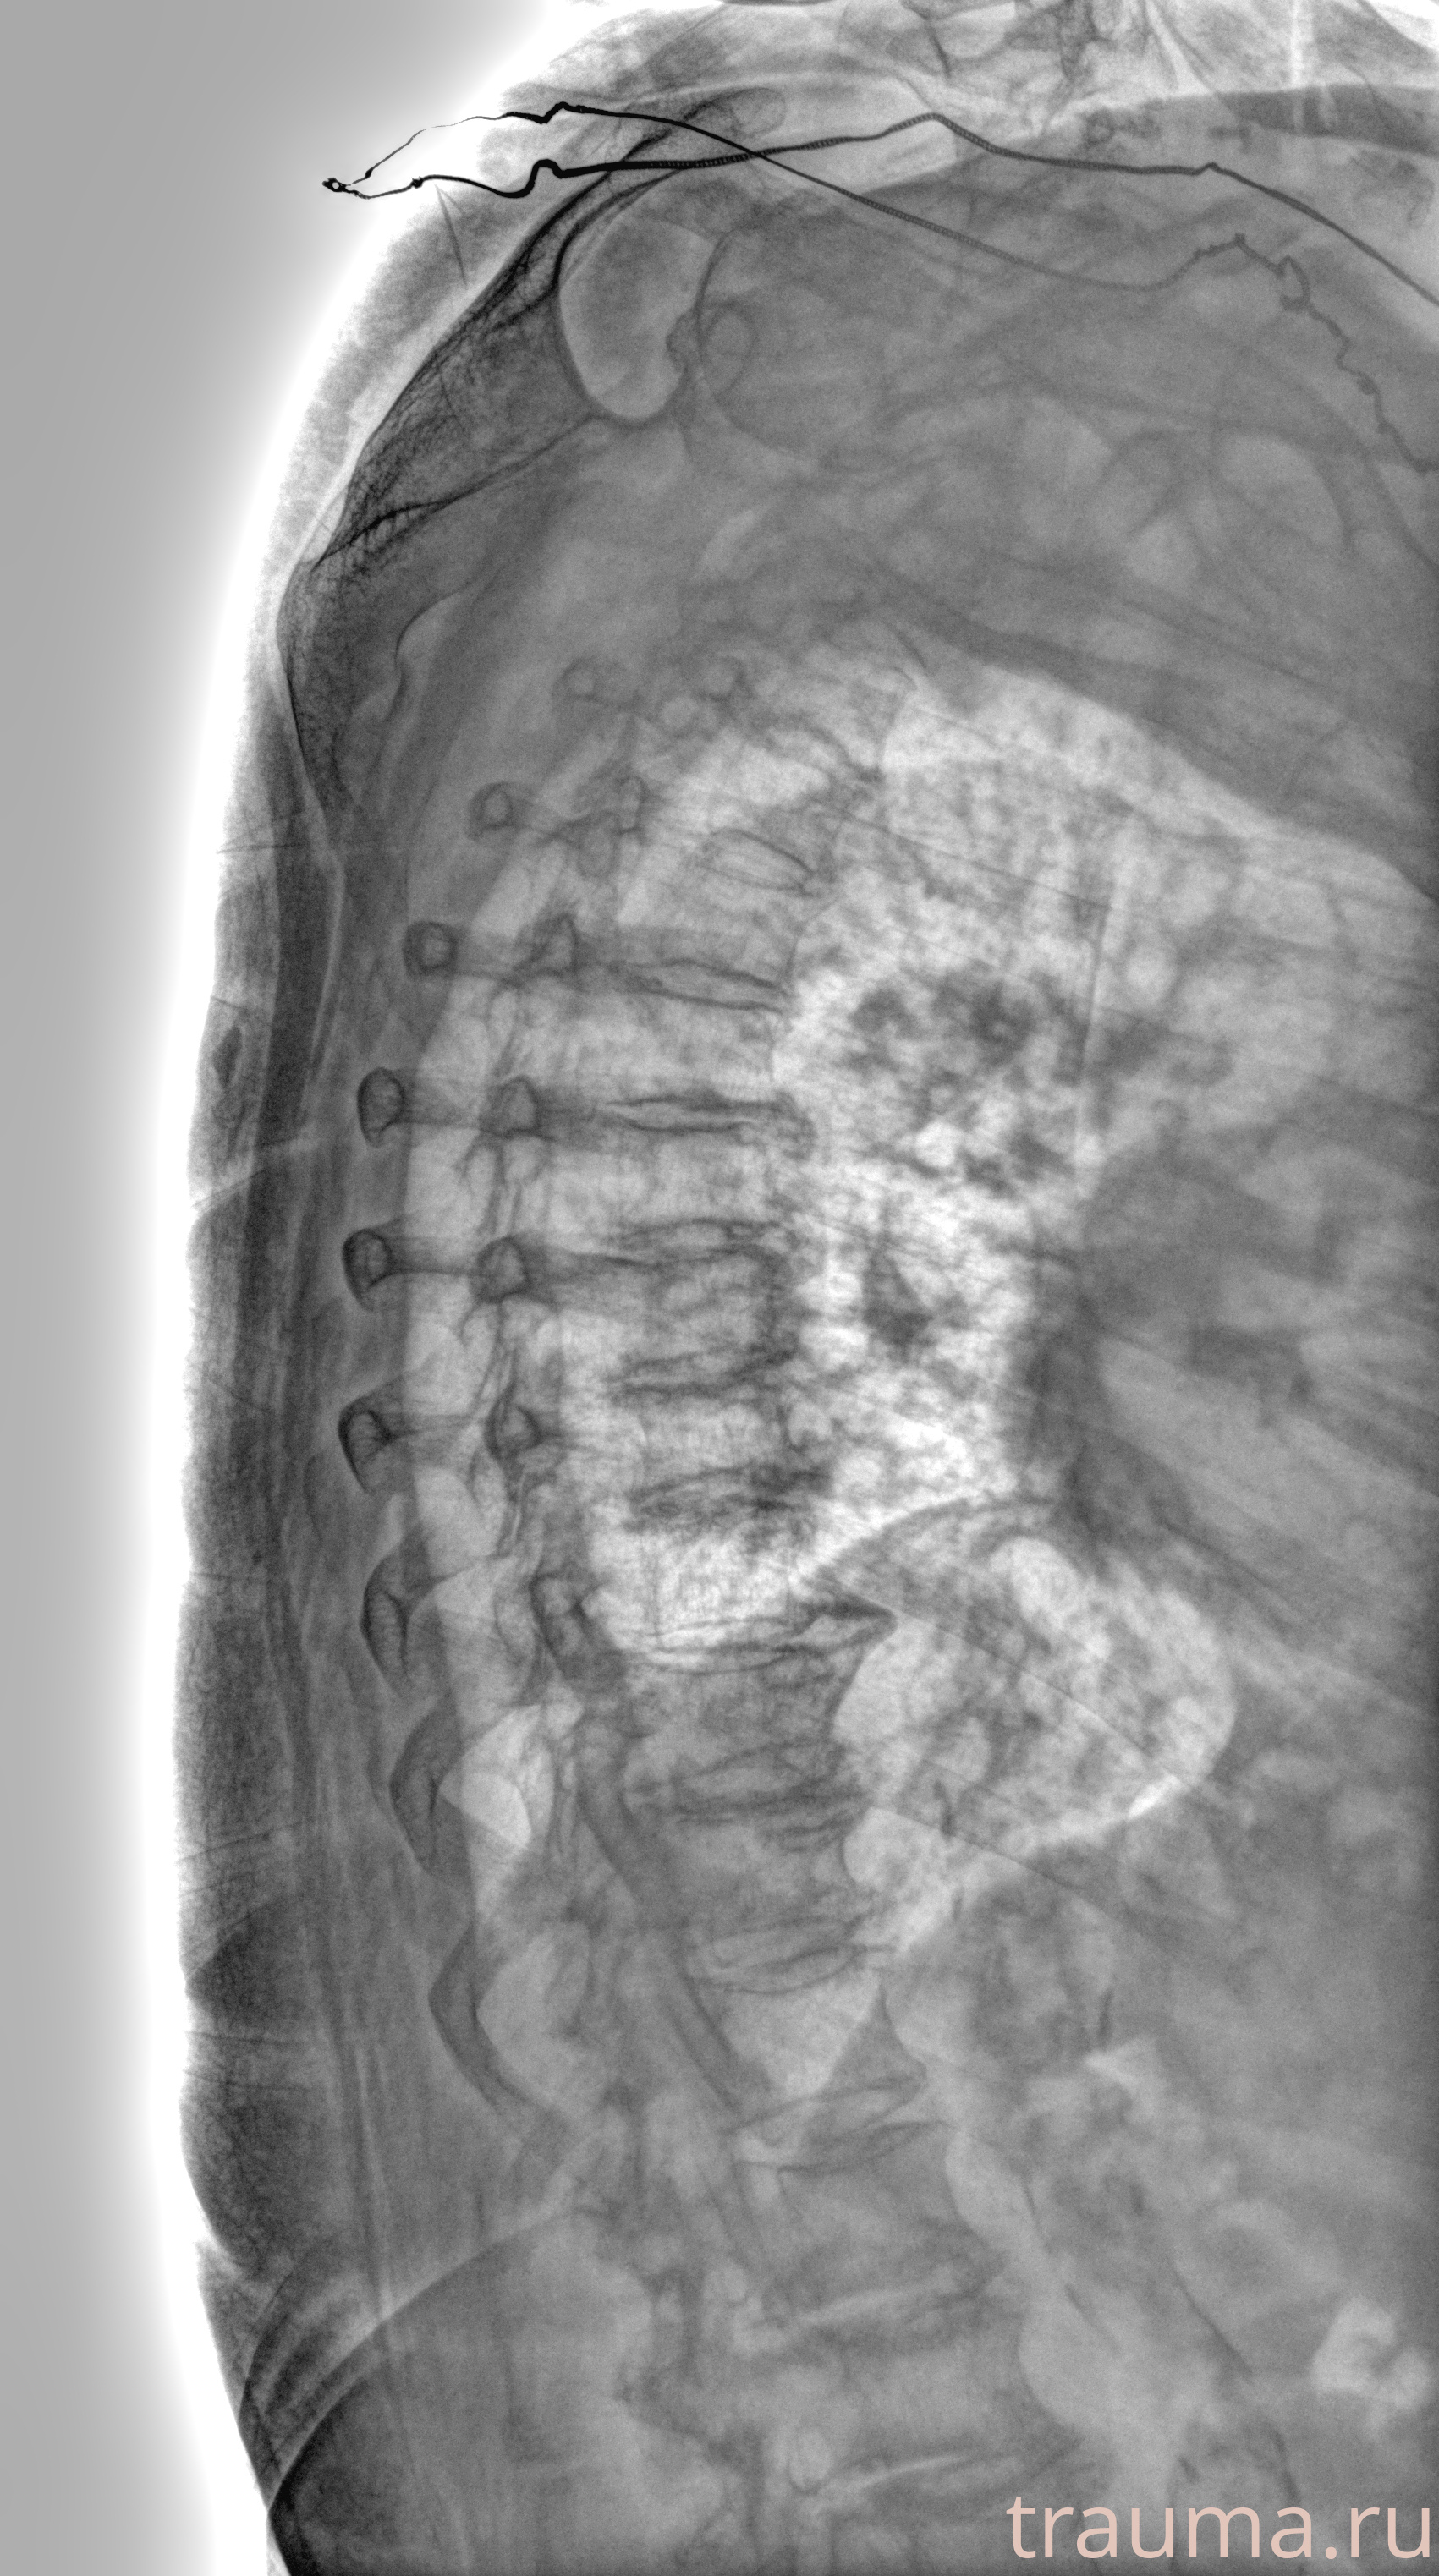

Рентген на дому: по вашему адресу приезжает врач-рентгенолог, травматолог-ортопед с мобильным рентгеновским аппаратом, проводит диагностику травмы или заболевания, делает необходимые рентгенограммы, дает рекомендации по дальнейшему лечению. Получить качественные снимки в домашних условиях возможно благодаря уникальной методике, разработанной МосРентген Центром для института  Склифосовского